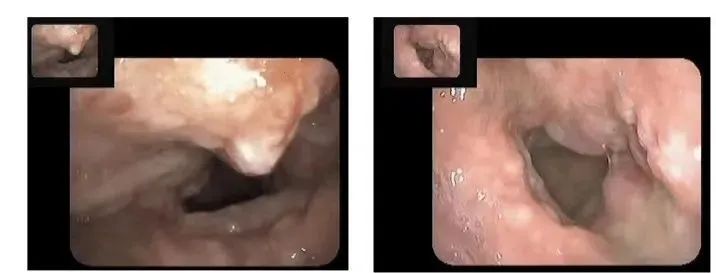

原本光滑的喉部,被肿瘤细胞占据

潘先生随即入院输液治疗。第一个周期的第4天,潘先生自觉“能说话了,说话有声音了。”同时颈部淋巴结明显缩小。1个周期治疗结束,喉镜提示喉腔内肿瘤已经缩退一半,同时淋巴结也大幅度缩小。

又经过1周期的治疗,喉腔内肿瘤和颈部肿大淋巴结已经完全消失。

喉镜下,肿瘤得到有效控制,喉部肿瘤逐渐消失